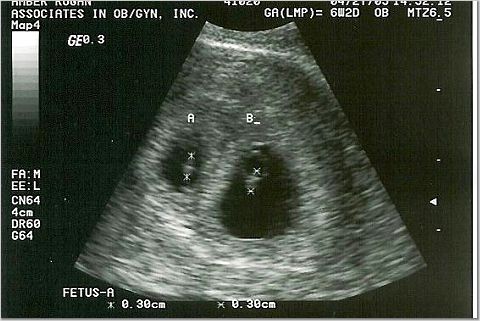

6 weeks - 3 millimeters

Heart rates 103 & 107